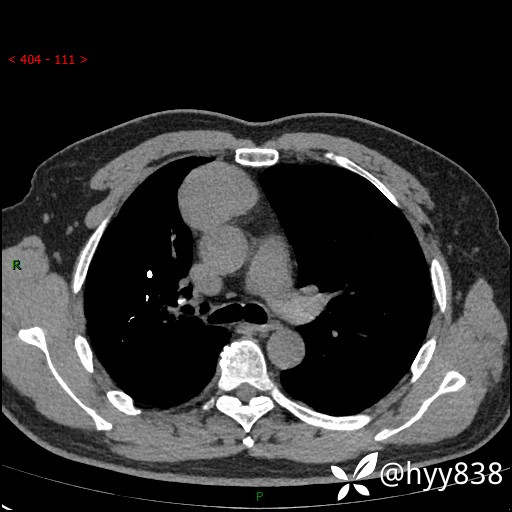

动脉期+静脉期

各期CT值